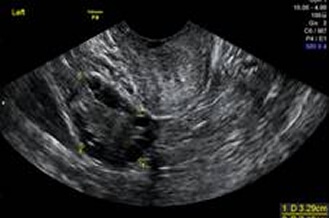

子宮筋腫